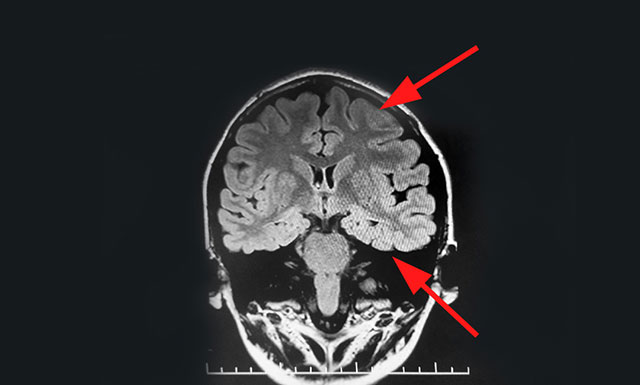

经检查,脑电监测崔丽华主任根据脑电图监测分析指出,患者双侧有癫痫波,左侧较为严重。磁共振检查,患者颞叶、额叶、海马结构异常。既往史显示,患者4个月时有肺炎高热病史,并伴有抽搐等症状。

患者经系统内科药物治疗不佳,确诊为药物难治性癫痫,经过系列检查最终明确患者致癫灶位于左侧海马、左侧颞叶、左侧额叶。手术指征明确,未见明显手术禁忌症。